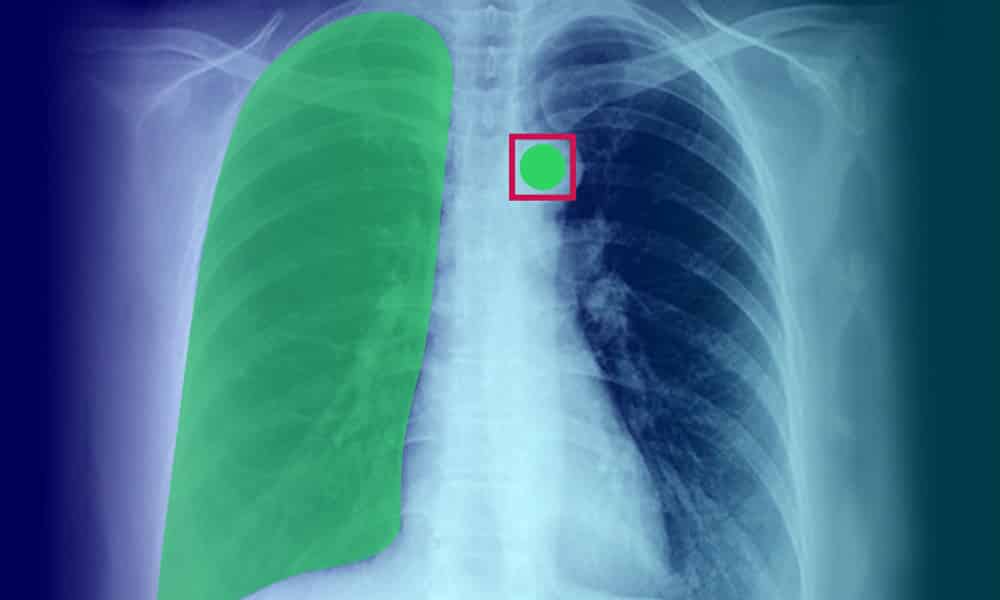

Image Data

Visual information in the form of photographs, medical scans, sketches, or technical drawings. For instance, medical imaging datasets include X-rays, CT scans, and MRIs that require precise annotation for AI-powered diagnostic systems.

Consider a patient diagnosis system: a unimodal model analyzing only text records might miss critical visual indicators from X-rays or subtle audio cues from heart examinations. By incorporating multimodal training data, AI systems can synthesize information from patient records, medical imaging, audio recordings from stethoscopes, and sensor data from wearables—creating a comprehensive health assessment that mirrors how human doctors evaluate patients.